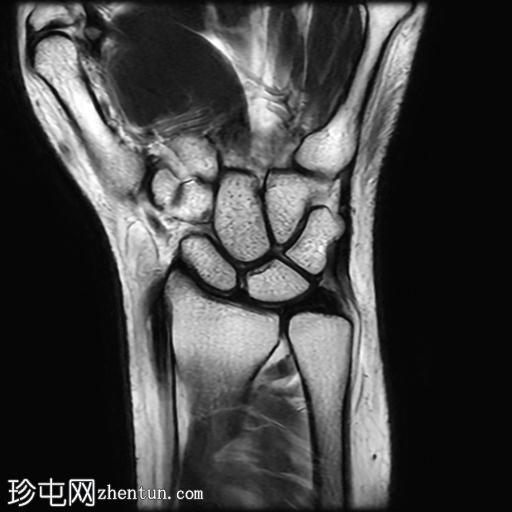

冠状面PD值

脂肪饱和度

MRI显示腕部第一背侧肌腱(拇长展肌和拇短伸肌)增厚,并伴有异常增厚的实质内液体信号。腱鞘内液体增多。

尺侧腕伸肌腱可见异常线性实质内液体信号增多,与板状间质撕裂相关。

MRI表现和临床表现提示De Quervain腱鞘炎。